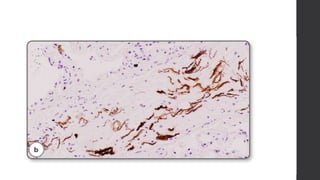

Stains used:

 H & E

 Alcian blue (amniotic acid mucin)

 LP 34 (high molecular wt keratin)

 Endothelial CD31 (diff b/w embolic squames &

sloughed endothelial cells)

Important autopsy pathologyis in the lungs. Stains used:  H & E  Alcian blue (amniotic acid mucin)  LP 34 (high molecular wt keratin)  Endothelial CD31 (diff b/w embolic squames & sloughed endothelial cells)